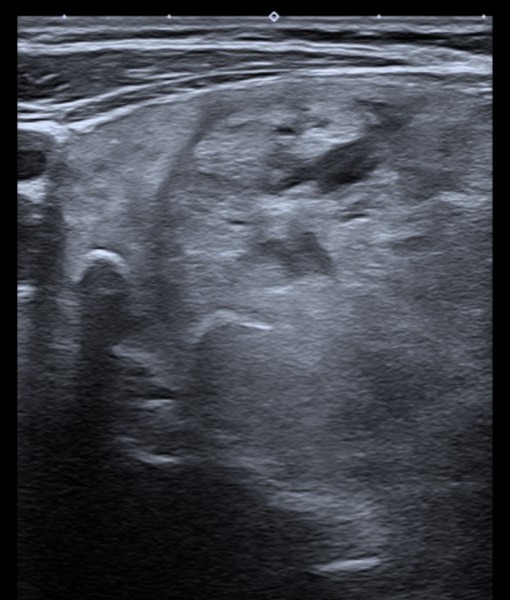

Ausencia de lóbulo izquierdo e istmo, en relación con cambios postquirúrgicos. Lóbulo tiroideo derecho aumentado, ocupado por conjunto de nódulos de aproximadamente 55 × 33 × 70 mm. Múltiples nódulos sólidos de ecogenicidad similar al parénquima; en Doppler se observa vascularización periférica. No se identifican adenopatías.

Se solicita ecografía preferente, cuyas conclusiones coinciden con las observadas: hallazgos compatibles con TI-RADS 3.